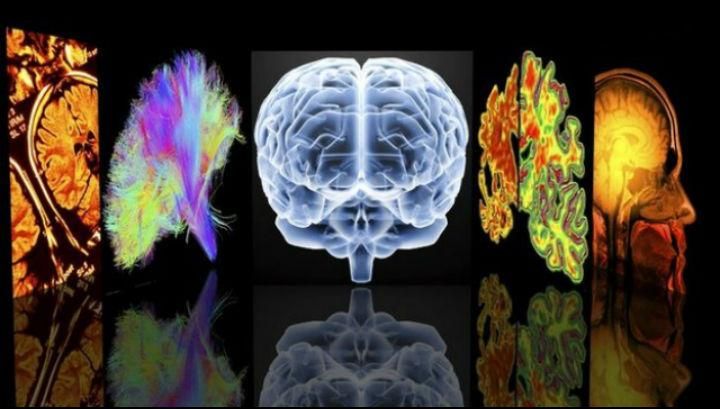

Спершу органи сканували за допомогою МРТ, а потім провели аутопсію. 12 донорських органів показали ознаки традиційного розсіяного склерозу, ще 12 – симптоми нового підтипу. Його назвали міелокортікальним розсіяним склерозом.

Обидва типи склерозу спричинили порушення у спинному мозку і корі, проте пошкодження білої речовини проявилося тільки в мозку з відомим типом – розсіяним склерозом.

Зрізи мозку з традиційним розсіяним склерозом (зліва) і міелокортікальним розсіяним склерозом (праворуч)

В обох випадках спостерігались ознаки, характерні для дегенерації мозку – зменшилися щільність нейронів і товщина кори. Тобто втрата нейронів при новому підтипі розсіяного склерозу може відбуватися і без поразки мієлінової оболонки.